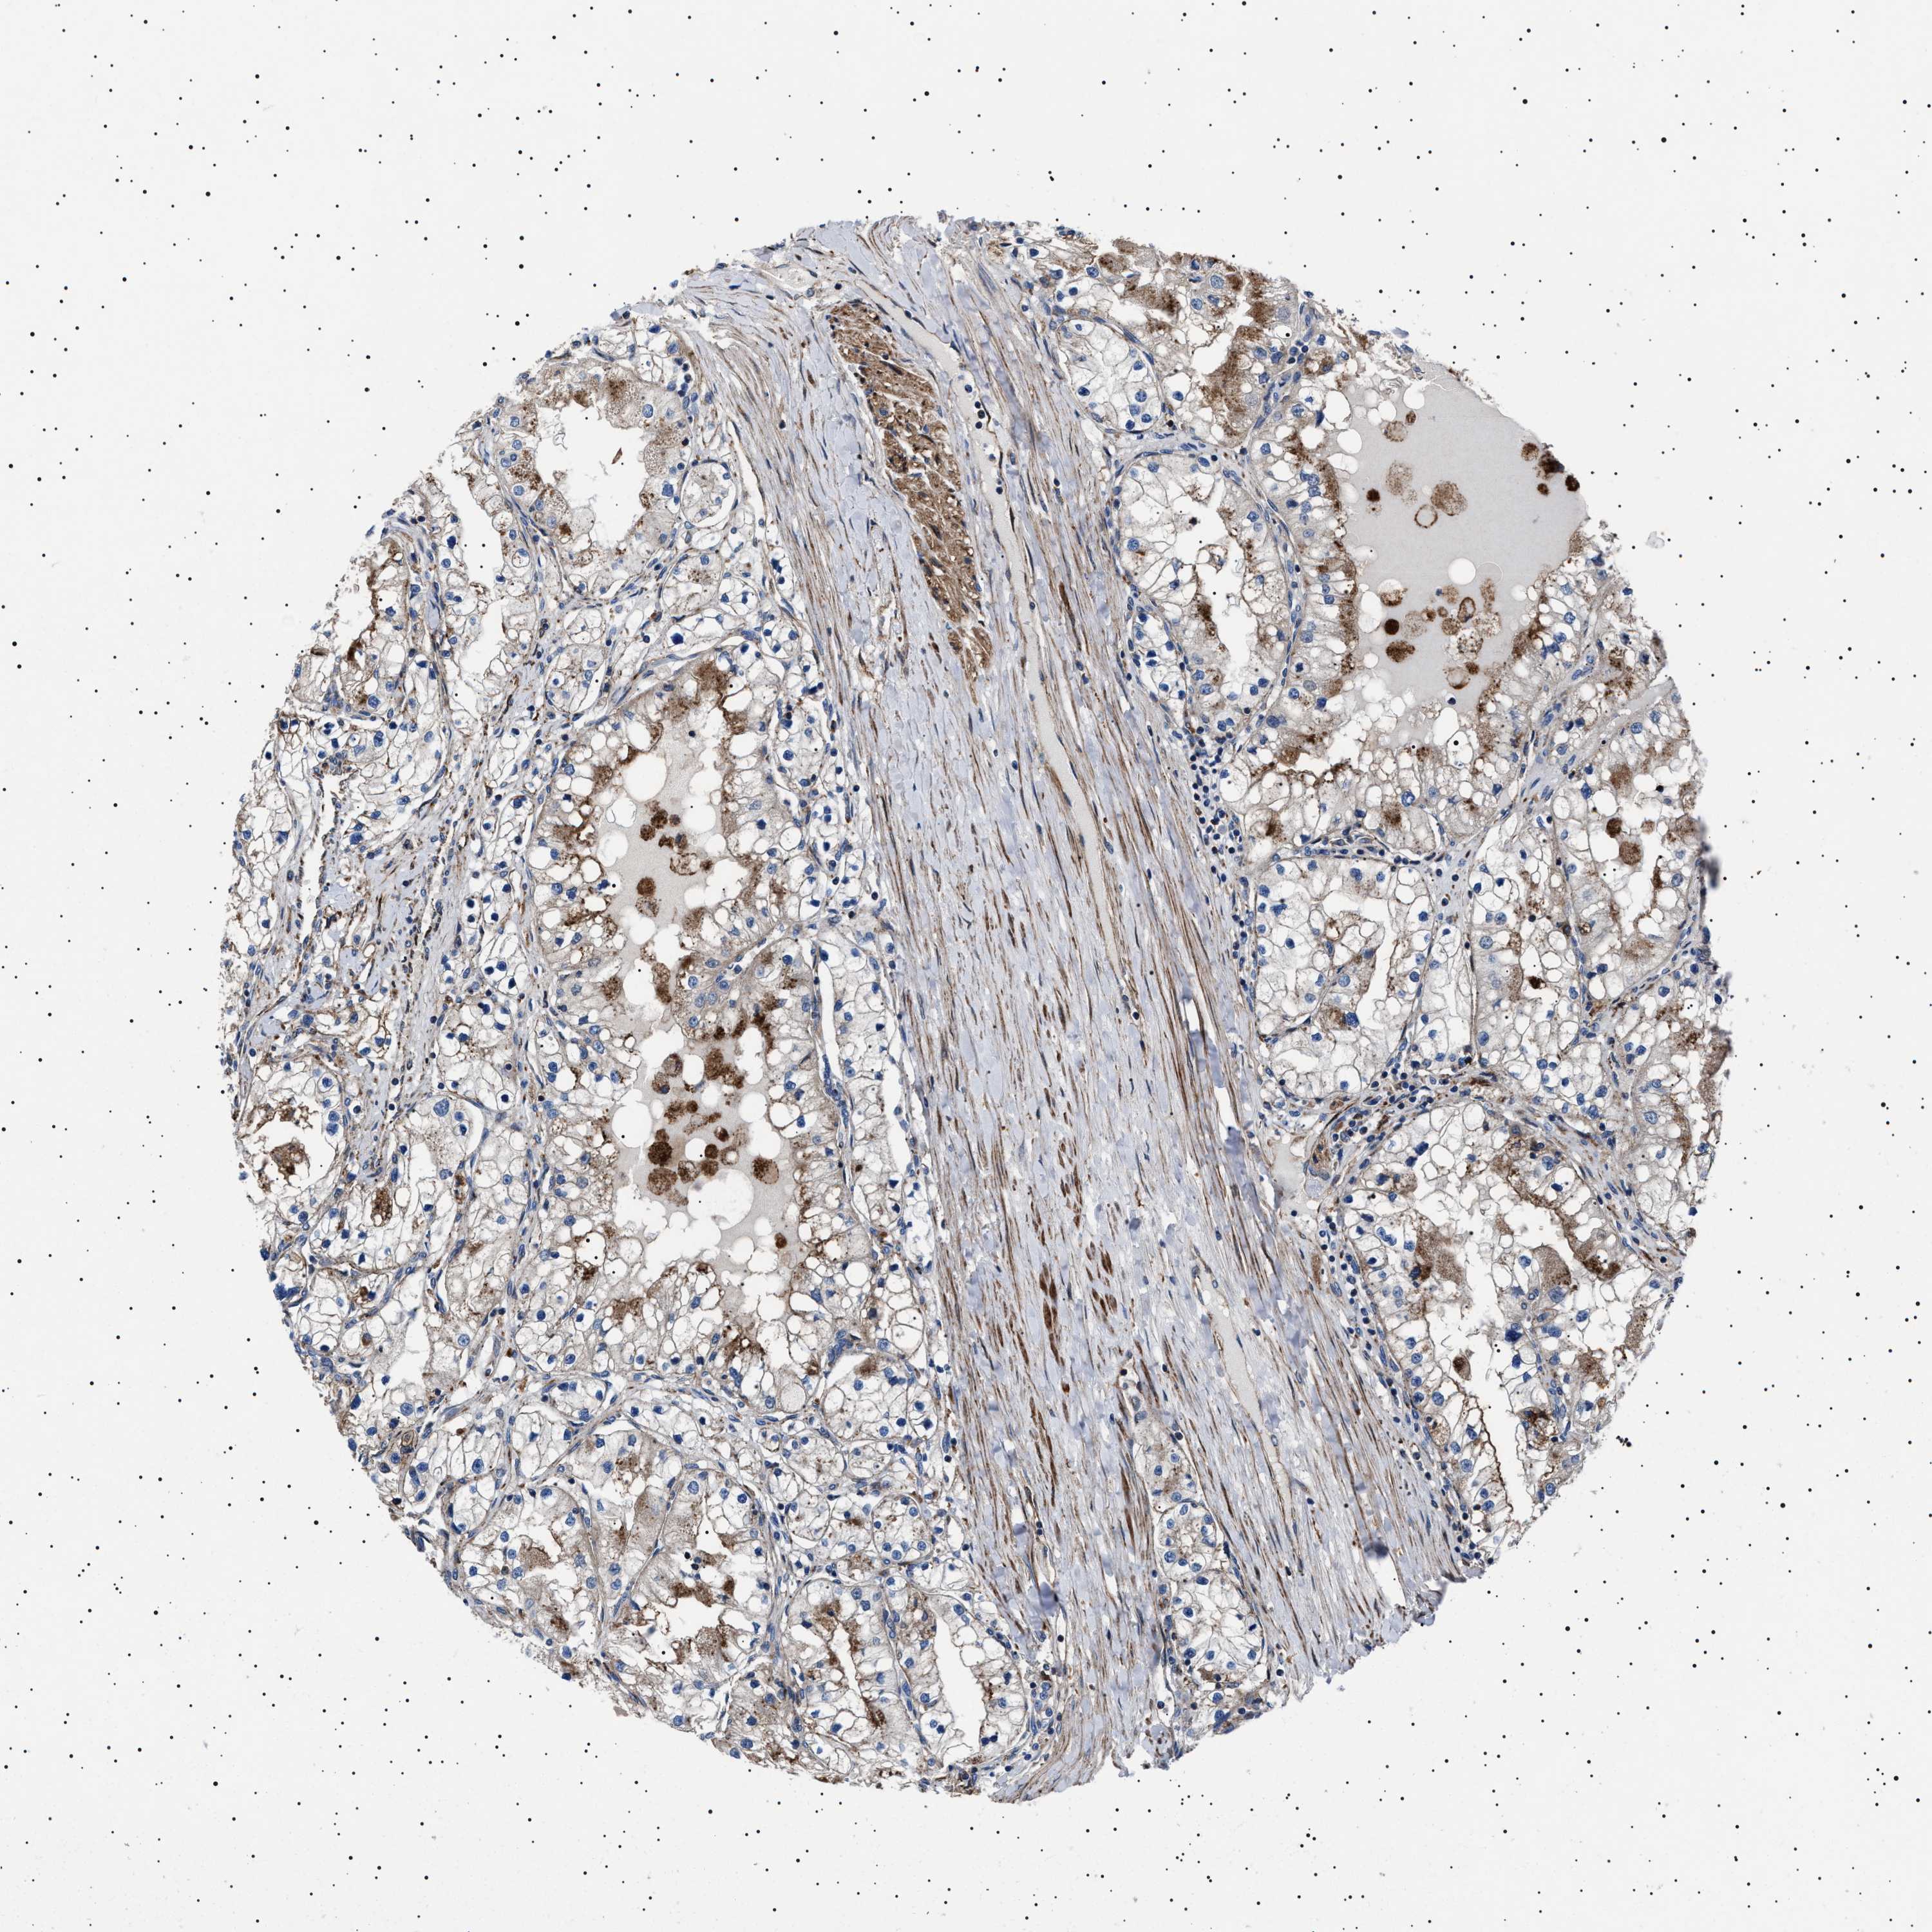

KIDNEY RENAL CLEAR CELL CARCINOMA (VALIDATION) - Interactive survival scatter ploti

The Survival Scatter plot shows the clinical status (i.e. dead or alive) for all individuals in the patient cohort, based on the same data that underlies the corresponding Kaplan-Meier plots. Patients that are alive at last time for follow-up are shown in blue and patients who have died during the study are shown in red.

The x-axis shows the expression levels (FPKM) of the investigated gene in the tumor tissue at the time of diagnosis. The y-axis shows the follow-up time after diagnosis (years). Both axes are complimented with kernel density curves demonstrating the data density over the axes. The top density plot shows the expression levels (FPKM) distribution among dead (red) and alive patients (blue). The right density plot shows the data density of the survived years of dead patients with high and low expression levels respectively, stratified using the cutoff indicated by the vertical dashed line through the Survival Scatter plot. This cutoff is automatically defined based on the FPKM cutoff that minimizes the p-score. The cutoff can be changed by dragging the vertical line or by entering a cutoff value in the square labeled "Current cut-off".

Under the Survival Scatter plot the p-score landscape (black curve; left axis) is shown together with dead median separation (red curve; right axis). Dead median separation is the difference in median mRNA expression between patients who have died with high and low expression, respectively. It is calculated as follows: median FPKM expression of dead patients with high expression - median FPKM expression of dead patients with low expression. This is intended to aid the user in visually exploring custom cutoffs and the associated p-scores and dead median separation.

Individual patient data is displayed and can be filtered by clicking on one or more of the category buttons on the top of the page. Categories describing expression level and patient information include: high, low, alive, dead, female, male and tumor stages. The scale of the x-axis can be toggled between linear and log-scale by clicking on the "x log" button. Mouse-over function shows TCGA ID, patient information and mRNA expression (FPKM) for each patient.

& Survival analysisi

Kaplan-Meier plots summarize results from analysis of correlation between mRNA expression level and patient survival. Patients were divided based on level of expression into one of the two groups "low" (under cut off) or "high" (over cut off). X-axis shows time for survival (years) and y-axis shows the probability of survival, where 1.0 corresponds to 100 percent.

NEU1 is not prognostic in Kidney Renal Clear Cell Carcinoma (validation)

Best expression cut offi

Based on the FPKM value of each gene, patients were classified into two groups and association between prognosis (survival) and gene expression (FPKM) was examined. The best expression cut-off refers the FPKM value that yields maximal difference with regard to survival between the two groups at the lowest log-rank P-value. Best expression cut-off was selected based on survival analysis .

When clicking on this number, the vertical dashed line indicating cut-off, the interactive survival plot, and the Kaplan-Meier curve will be adjusted to show results based on the best expression cut-off.

: 1.09

TCGA RNA samplesi

RNA-seq data is reported as average FPKM (number Fragments Per Kilobase of exon per Million reads), generated by the The Cancer Genome Atlas (TCGA) .

Normal distribution across the dataset is visualized with box plots, shown as median and 25th and 75th percentiles. Points are displayed as outliers if they are above or below 1.5 times the interquartile range. FPKM values of the individual samples are presented next to the box plot.

Average pTPM 1.4

Number of samples 100